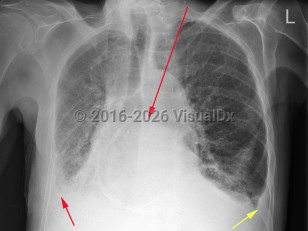

- Airway / Breathing: Often, positive end-expiratory pressure (PEEP) is required via a continuous positive airway pressure (CPAP) or bilevel positive airway pressure (BiPAP) machine for increased work of breathing, hypoxia, or evidence of pulmonary edema on examination or imaging.